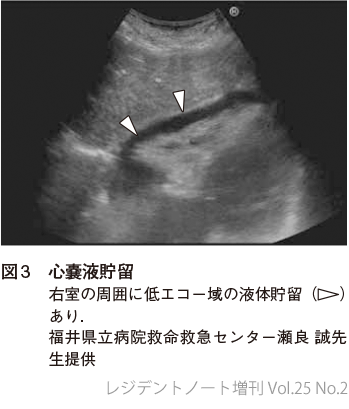

心室壁よりも外側に液体貯留があるかどうか確認する(図2,3).

1. 心窩部像

EFASTではまず心窩部像で心嚢液貯留の有無を確認する.心嚢液貯留から心タンポナーデに至ると閉塞性ショックを呈するが,これは外傷において最も多い出血性ショックとは治療方針が大きく異なるため,その認知は重要である.なお,心嚢液貯留は心タンポナーデの必要条件であるが十分条件ではない.